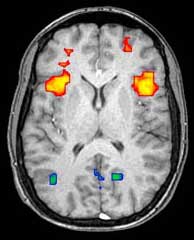

التصوير بالرنين المغناطيسي الوظيفي

Axial MRI slice at the level of the basal ganglia, showing fMRI BOLD signal changes overlayed in red (increase) and blue (decrease) tones.

ويمكن للتصوير الوظيفي، على سبيل المثال، معالجة المعلومات عن طريق مراكز في المخ ليتم تصويرها مباشرة. مثل معالجة المنطقة المصابة في المخ والمسئولة عن زيادة الأيضا والتي تظهر مضيئة في المسح. وأحد الاستخدامات المعرفية للتصوير الوظيفي هي استخدامه في التعرف على الأفكار أو قراءة الفكر.